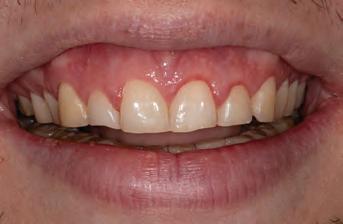

A 31-year-old woman presented with cosmetic concerns regarding her smile and requested a conservative enhancement. After clinical and radiographic analysis, digital 35mm photographs were taken and reviewed by the restorative clinician, technician, and surgeon (Fig 1). A digital impression was taken of the maxillary and mandibular arches using an intraoral scanner (Trios 3, 3Shape; Fig 2), and a smile design was developed with NemoSmile Design 3D software (Nemotec; Fig 3a). This allows for a facially driven smile frame to be created using reference lines of facial and smile proportions and natural teeth shapes and textures from the digital library (Fig 3b).

After developing the simulated mock-up, a 3D-printed resin model was created using CAD software (Fig 4a), and a clear PVS matrix (Exaclear, GC America) was fabricated to replicate the printed diagnostic wax-up using a nonperforated tray (Fig

Fig 1 Preoperative clinical views of a 31-year-old woman presenting with diastemas and limited tooth visibility. (top) Portrait. (center row) Intraoral views. (bottom row) Smile.

4b). This matrix was used to create an intraoral motivational mock-up with bis-acryl composite (Luxatemp Ultra, DMG). This additive mock-up provides the interdisciplinary team with an intraoral translation for evaluation (Fig 5). Upon evaluation of the digital smile frame and the clinical translation, it was determined that multiple esthetic and restorative requirements were necessary for an optimal biologic framework, and the interdisciplinary team determined the best sequence for these procedures. The patient was presented with the interdisciplinary treatment possibilities that included restoring the maxillary anterior teeth and premolars with a minimally

invasive preparationless procedure or with less conservative veneer preparations. The restorative materials discussed included injectable resin composites and ceramic (ie, feldspathic, pressable, machinable). For an optimal biologic framework and health, it was determined that connective tissue grafting would be necessary for treatment of the recessiontype defects on the maxillary left central and lateral incisors, canine, and premolars. The patient opted for the conservative preparationless composite veneers using the injectable resin technique followed by a connective tissue surgical procedure using the tunneling technique.